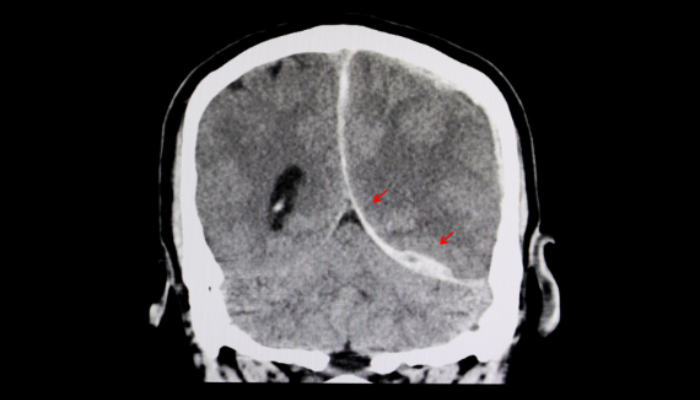

É um dos exames iniciais mais utilizados em caso de detecção do acidente vascular cerebral, o AVC, popularmente conhecido como derrame.

A TC fornece imagens detalhadas do cérebro do paciente, permitindo a visualização de sangramentos, coágulos e outros sinais de AVC.

Traumatismos cranianos e inchaços cerebrais

Por fornecer imagens detalhadas do crânio e do cérebro, a TC também é uma ferramenta crucial para o médico no diagnóstico e tratamento de traumatismos cranianos e inchaços cerebrais.

- hemorragias,

- hematomas.

Hidrocefalia

A tomografia de crânio também é usada como exame complementar no diagnóstico da hidrocefalia, na avaliação da extensão da condição e em alguns casos na identificação da causa, seja em bebês, crianças ou adultos.

O exame permite visualizar mais detalhadamente a estrutura do cérebro, incluindo os ventrículos, que são espaços preenchidos com líquido cefalorraquidiano